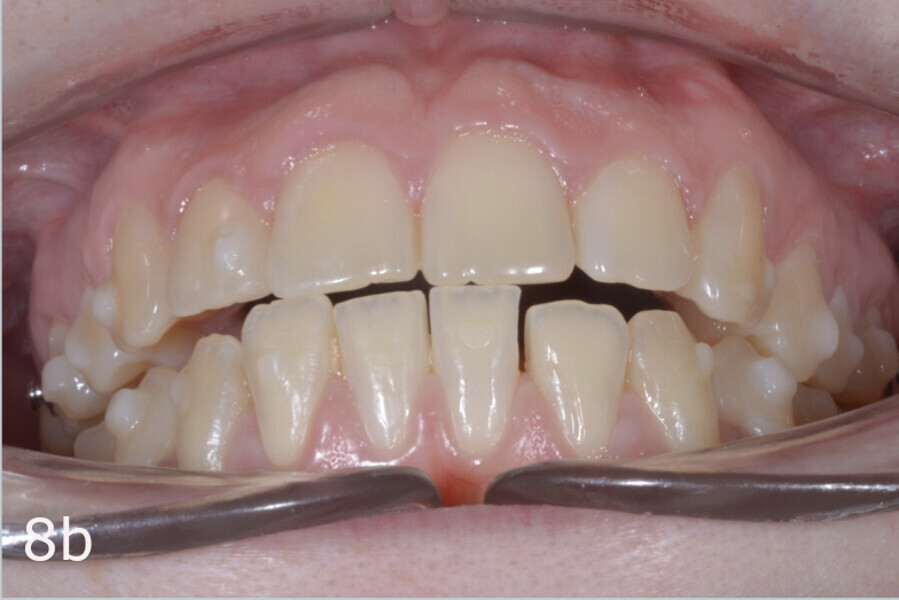

The 23-year-old dolichofacial female patient complained of not being able to chew properly. Facial examination showed a convex profile, an enlarged lower facial height, and a skeletal Class III malocclusion (Figs. 1–3). Intra-oral examination revealed an Angle Class III right subdivision malocclusion, anterior open bite, no overjet and a maxillary dental midline deviated about 3 mm to the right compared with the mandibular dental midline (Fig. 4). The panoramic radiograph confirmed previous extraction of the maxillary right first premolar and the presence of all four third molars (Figs. 5 & 6).

The treatment objectives included closing the anterior open bite, achieving a bilateral Angle Class I relationship and a proper overjet and overbite, correcting the midline discrepancies, and achieving a profile harmonisation. The treatment plan consisted of orthodontic camouflage treatment with asymmetric distalisation in three of the four quadrants using Invisalign aligners (Align Technology) and third molar extraction. The Invisalign Comprehensive package was chosen, and 63 pairs of aligners were used (Figs. 7–10). Each aligner was worn for 20 hours a day for one week each. The use of Class III elastics on both sides was indicated. Afterwards, ten refinement aligners were needed to improve the interdigitation on the right side (Figs. 11 & 12).